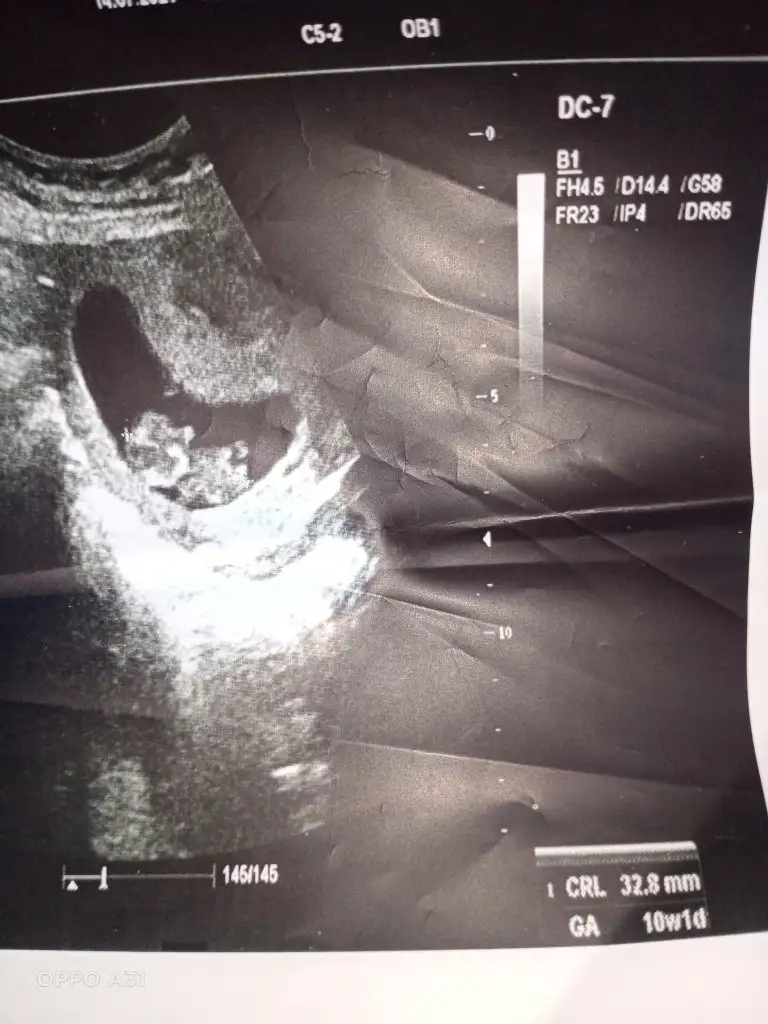

Benim bebeğime de bakar mısınız 9 buçuk haftalık. Belki erken ama bir yorumunuz olursa diye merak ediyorumEn iyi 11 12 13 haftalar olmalışimdilik erkek yönünde ama yanıltabilir dediğim haftalar olmalı

Erkek görünüyor

Şimdilik erkek yönünde ama en iyi 11 12 13 haftalar olmalı tekrar USG paylasinBenim bebeğime de bakar mısınız 9 buçuk haftalık. Belki erken ama bir yorumunuz olursa diye merak ediyorum